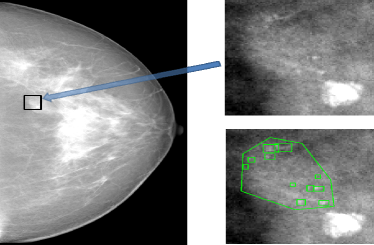

One application of such a knowledge transfer problem is the detection of microcalcification (MC) groups in 3D digital breast tomosynthesis (DBT). A MC group is composed of multiple small and similar individual MCs, and is considered a possible sign of breast cancer. Because MCs may be small and lack enough contrast (as in Figure 1(a)), they can be easily missed by radiologists during the routine screening process. Needless to say, a MC group computer-aided detection (CAD) can help radiologists locate suspicious regions and help them make diagnostic decisions.

A large number of literature has been reported on creating CAD system for MC groups in 2D mammography (as in Figure 1(a)). However, publications on CAD for recently emerged DBT (as in Figure 1(b)) are very limited. This is due to the difficulty of collecting enough cancer cases to train a DBT CAD from scratch. Instead, most researchers built systems on small DBT datasets with limited training [1, 2] or applied a mammography CAD directly on slices or projections of DBT volumes [3, 4, 5].

The proposed CAD were first evaluated on a separate GE Senographe projection image dataset with and truthed biopsy-proven malignant MCs and MC groups. The candidate generator provided sensitivity to individual MCs with FPs per image. Figure 3 shows the free-response receiver operating characteristic (FROC) curves of the test set from the outputs of the three pre-trained classifiers.